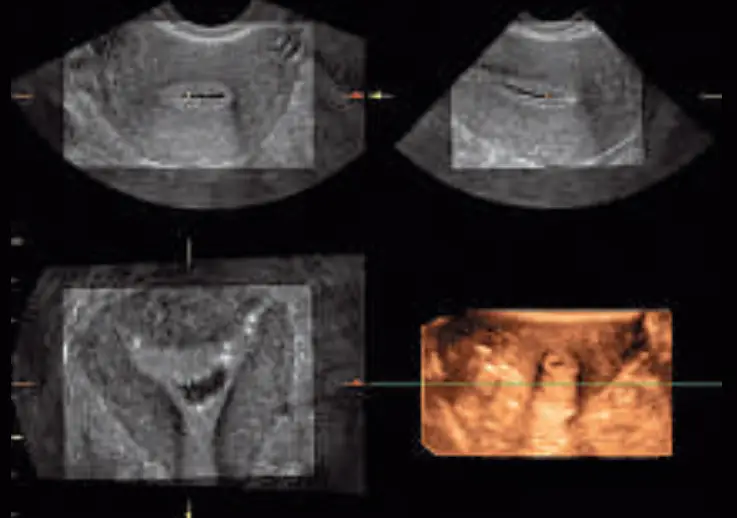

Varicose vein displayed using Easy 3D; additional clinical information about the C-plane and the course of the vessel can be collected while acquiring a 3D image

3D volume acquisition of the uterus using the 4DE7C probe during saline Infusion Sonography (SIS) procedure

Real-time 4D Imaging. Acquire and constructs volumetric images, displaying multiplanar views of the anatomy. See anatomical relationships not visualized otherwise.